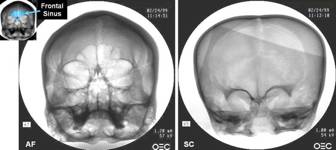

1999. The first scientific test of the skull was a radiographic X-ray analysis carried out in Las Vegas, Nevada. The weird skullbone was shown to be uniformly thin throughout, rather than exhibiting the usual thinness in areas of deformity while being otherwise normal. Also, no sign of frontal sinuses were visible, not even vestigial buds. This was considered highly unusual. The most striking result, however, was that the associated piece of upper right maxilla had impacted teeth in it, indicating that the skull had belonged to a child in the range of five or six at death. Based on that seemingly solid piece of evidence about it, we named it the Starchild.

Denver. The turning point for me came in Denver, Colorado, when a brain specialist made a number of startling discoveries about the Starchildbrain. (This doctor made a specific request that I not name him.) First, its capacity was astounding. Normal human adult craniums contain an average of 1400 cubic centimeters of brain matter. A small-stature adult or a child of about twelve which was the Starchildsize would have a brain in the range of 1200 cc. The Starchild had a brain volume of 1600 cc, which baffled the specialist. Even considering the extreme shallowness of the eye orbits, the missing frontal sinuses, and the expansion of the parietals, he could not account for an increase of fully 1/3 the normal human volume.